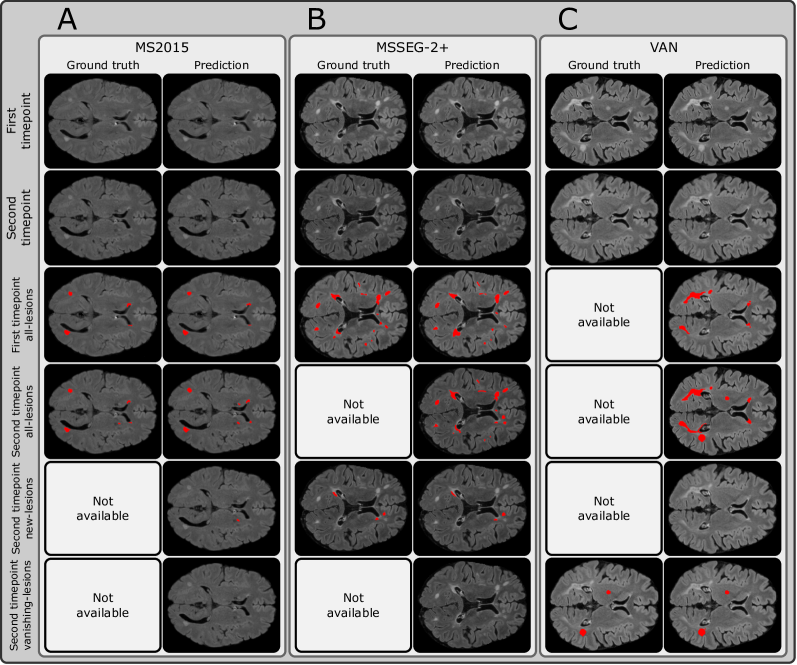

Refer to caption

Figure 3: SegHeD is capable of simultaneous multi-task segmentation (Rows 3 to 6). Some tasks do not show new/vanishing-lesions predictions as they are not present at the given slice. "Not available" denotes no ground truth annotation for comparison. A: Dataset where all-lesion labels are available for first and second timepoints. B: Dataset where first timepoint all-lesion label and second timepoint new-lesion label are available. C: Dataset where second timepoint vanishing-lesion label is available.